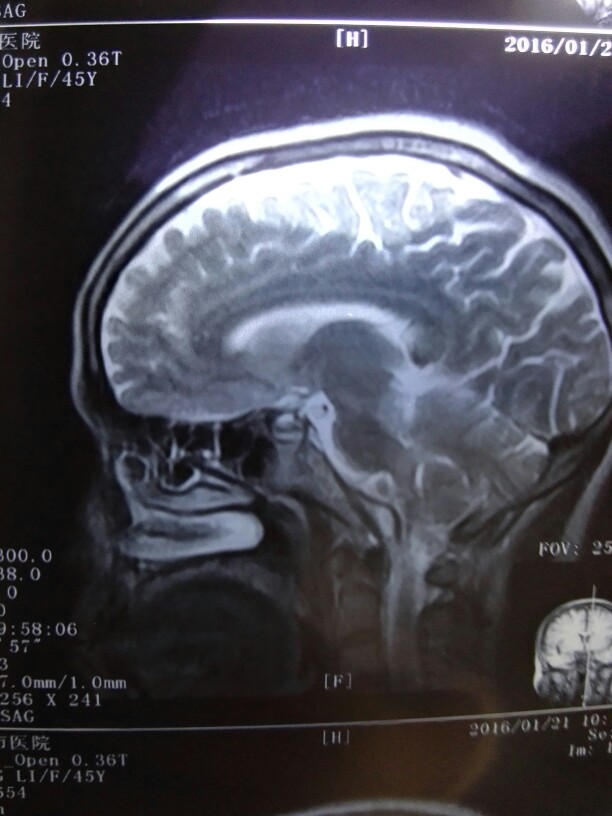

女性,45岁,头晕头痛半月。伴有鼻涕中带血丝。

关键看鼻咽部有问题吗?谢谢!